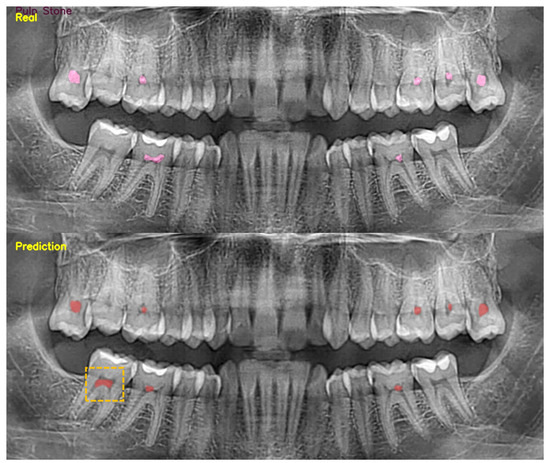

The Detection of Pulp Stones with Automatic Deep Learning in Panoramic Radiographies: An AI Pilot Study †

2. Material and Methods

3. Results